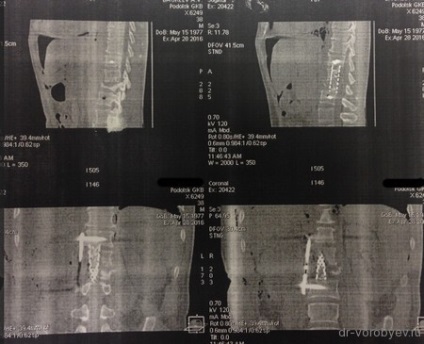

După un curs de detoxifiere și terapia masivă cu antibiotice pacientul a fost pregătit pentru o intervenție chirurgicală. Sa decis să efectueze îndepărtarea corpurilor vertebrale L1 L2 și discul între ele, iar placa corporodesis Masham umplut de os proprii (în acest caz, o margine) în China. Cel mai adesea, atunci când aveți nevoie pentru a manipula 1 vertebre vom trata accesul antero lateral deasupra sau dedesubtul diafragmei. În această situație, operarea cu cotorul de tranziție care implica doua fuziune vertebre apare între TN12 și L3, în total 4 trebuie să expună o vertebră și, prin urmare, a trebuit să folosească TORAKOFRENOLYUMBOTOMIYU. Accesul de-a lungul marginii cu deschiderea cavității pleurale și disectia retroperitoneale și diafragmei pe dreptul său semiperimetrul.

stadiu vizibil de funcționare după instalarea plasei între corpurile vertebrale. Operarea peste toracostomie placa spondylosyndesis (care a fost distrusă după ce a suferit purulent pleurita).

La filmele de control după implanturi chirurgie bună stare, decompresie este realizată în mod adecvat.